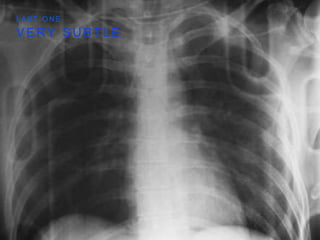

V E R Y S U B T L E

L A S T O N E

W H A T I S T H E D X ?

P T W I T H S E V E R E A S T H M A

T E N S I O N

P N E U M O T H O R A X

• NOTE THE TRACHEAL

DEVIATION

• ABSENCE OF LUNG

MARKINGS LEFT

• DEEP SULCUS SIGN

LEFT

V E RY S U B T L E L A S T O N E

W H AT I S T H E D X ? P T W I T H S E V E R E A S T H M A

T E NS I O N P N E U M O T H O R A X • NOTE THE TRACHEAL DEVIATION • ABSENCE OF LUNG MARKINGS LEFT • DEEP SULCUS SIGN LEFT